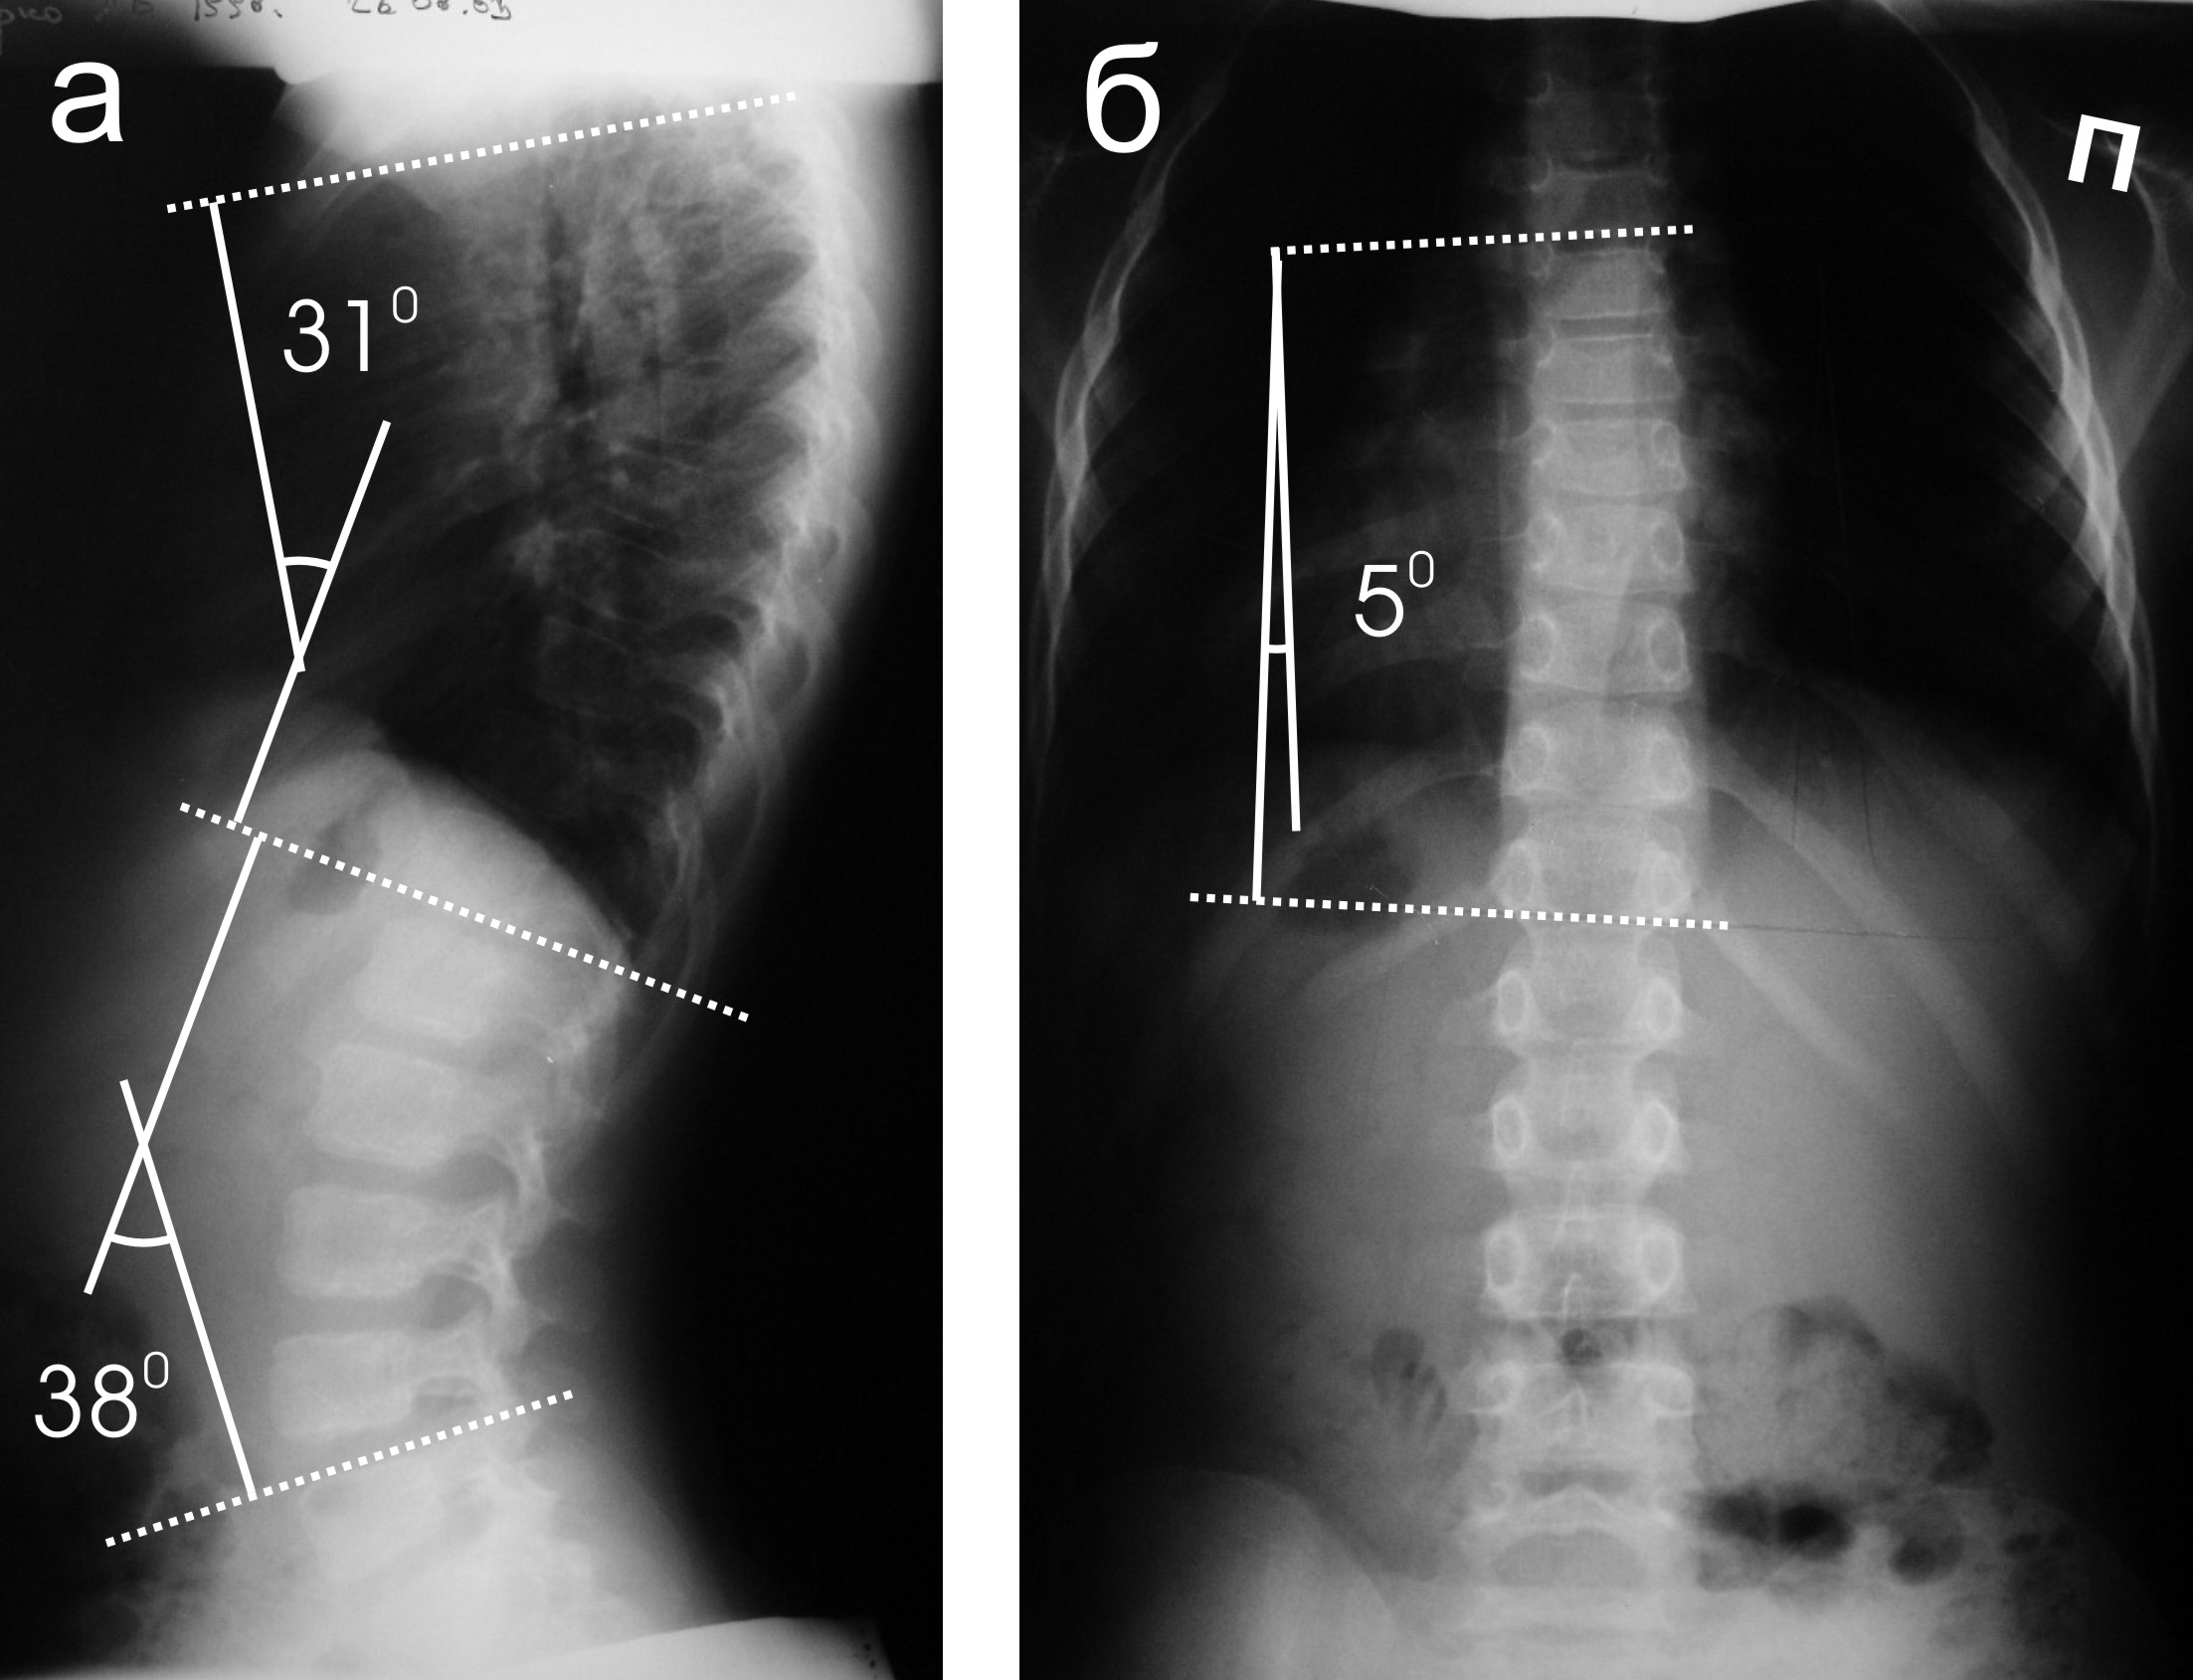

- При наличии сколиоза. Регулярные обследования важны для мониторинга прогрессирования заболевания.

- сколиоз;